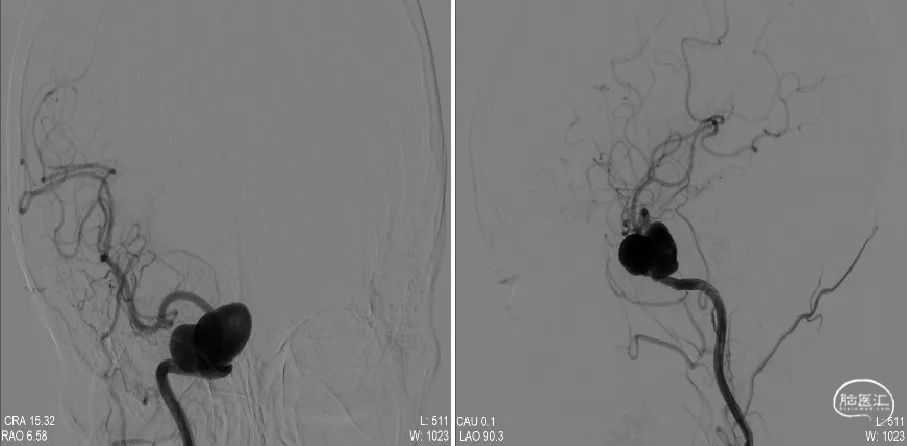

入院后行DSA造影:右侧颈内动脉海绵窦段巨大动脉瘤(27.7×16.6mm)、左侧颈内动脉床突旁动脉瘤(7.1×6.1mm)、前交通动脉瘤(2.6×2.2mm)。经科室讨论认为,右侧A1动脉缺如,左侧A1动脉供应双侧大脑前动脉,前交通动脉瘤血流冲击大,破裂风险较高,而右侧海绵窦段动脉瘤虽然瘤体巨大且形态不规则,但是风险相对较低,左侧床突旁动脉瘤同样风险较低。与患者商议后先行前交通动脉瘤支架辅助栓塞术。

3个月后,患者再次入院要求治疗右侧海绵窦段动脉瘤。术前DSA示:右侧颈内动脉海绵窦段巨大型动脉瘤,呈不规则囊状,瘤体大小约为:33.6mm×18.3mm,瘤颈约为:8.7mm,瘤体近端颈内动脉管径3.18mm,远端管径2.52mm。